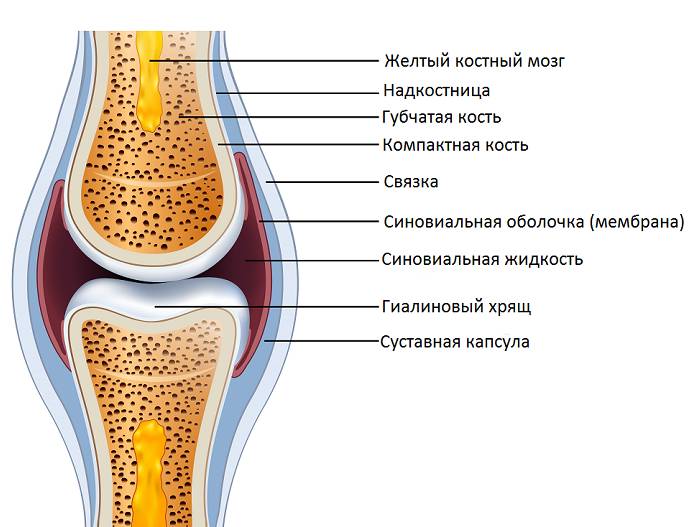

Чтобы понять, почему внутрисуставной перелом является особым видом перелома, необходимо представить себе анатомическое строение сустава.

Каждый сустав складывается из двух или более концов костей, которые соответствуют друг другу по форме суставной поверхности. Они соединены между собой с помощью капсулы и связок, которые являются соединительнотканными структурами.

Суставная капсула формирует полость сустава, которая отграничена от других анатомических образований, расположенных по соседству. Связки находятся внутри и снаружи капсулы – они удерживают кости и не позволяют им слишком далеко смещаться от изначального положения. Сами же концы костей покрыты хрящом – благодаря его естественной гладкости они способны беспрепятственно скользить друг относительно друга.

Внутри сустава (суставной полости) находится небольшое количество биологической жидкости – она выполняет роль смазки. Главные функции смазки это:

- облегчение скольжения суставных поверхностей;

- доставка питательных веществ к хрящевой ткани.

Все перечисленные анатомические структуры вместе образуют своеобразный шарнир, элементы которого зависят друг от друга. Поэтому если случился внутрисуставной перелом, нарушения будут касаться всех или практически всех структур сустава: